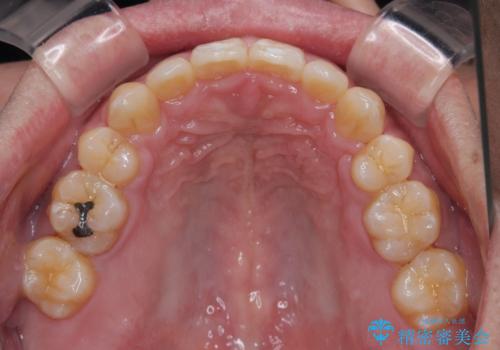

2年から2年半の治療期間を想定しており、予定通りの期間で無事に終了することができました。

唇や顎先に力を入れないなくてもスムーズに唇を閉じることができるようになりました。